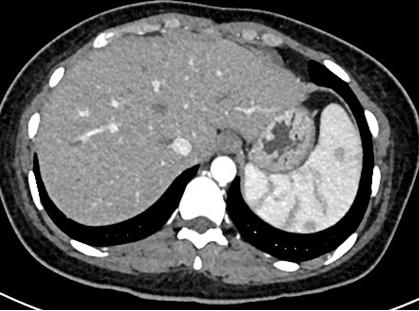

图2. 风湿免疫指标办好住院已经是1月13日下午四点了,介入科方淳主任及团队加班加点,当天晚上就为患者做了肠系膜动脉和静脉造影,结果没有发现大血管的问题,但是小血管充血、丰富,呈梳子样改变(称为“梳子征”,图1)。排除了肠系膜大血管的问题之后,高度怀疑肠系膜小血管炎可能,事不宜迟,赵家胜主任通过电话联系到风湿免疫科值夜班的王璇主治医生,王医生仔细询问了病史,了解到患者有过脱发和自发性流产的病史,结合本次肠道小血管炎的表现,高度怀疑系统性红斑狼疮引起的肠系膜血管炎。为了缓解患者的腹痛,挽救病人的生命,王璇医生基于对病情的判断,在化验结果尚未出来的情况下果断使用了糖皮质激素,第二天早上(1月14日)患者腹痛和恶心、呕吐即明显好转,患者胃口也开了,随后吃了点半流质,但下午又出现了腹痛和呕吐,这时化验结果也出来了(见图2),狼疮的标志性抗体-抗Sm抗体和ds-DNA抗体均阳性,证实了系统性红斑狼疮的诊断。赵主任和风湿免疫科汤建平主任共同查房后认为系统性红斑狼疮诊断明确,以急性腹痛起病,而且一发病就表现为狼疮危象的红斑狼疮少见,常规剂量激素疗效不佳,腹部CT结果显示肠壁水肿和胸腹水有进展(见图3、图4),需要立即进行大剂量激素冲击治疗。

图3. 1月15日CT肠壁增厚水肿(箭头所指)